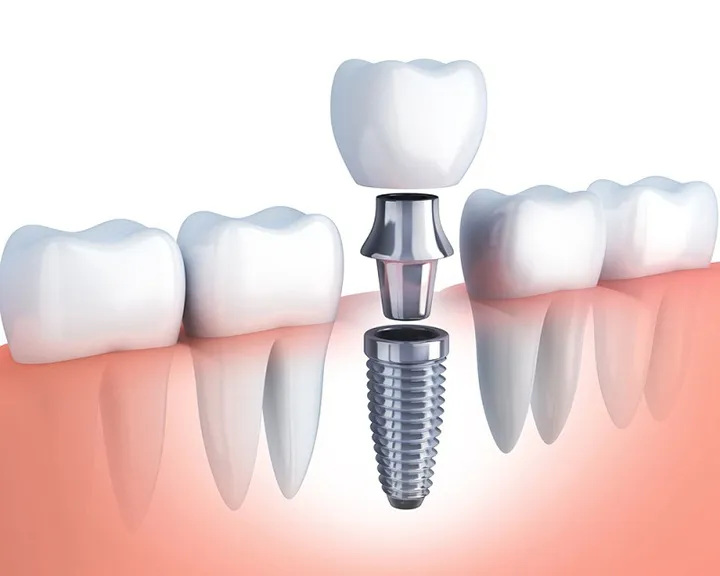

Khi bị viêm lợi nổi hạch, quá trình viêm sẽ làm nướu dần tách ra khỏi chân răng. Thông qua đó tạo ra khoảng trống giữa mô nướu và bề mặt răng. Nếu tình trạng viêm không được điều trị kịp thời, vi khuẩn sẽ phát triển mạnh mẽ. Sau đó chúng sẽ xâm nhập vào các mô nâng đỡ răng. Trong đó bao gồm mô lợi, dây chằng nha chu và xương ổ răng.

Sự nhiễm trùng này gây ra sự suy yếu của cấu trúc nâng đỡ. Điều này sẽ làm giảm khả năng bám chặt của răng vào xương hàm. Kết quả là răng sẽ trở nên lỏng lẻo, dễ bị lung lay. Cuối cùng có thể bị mất đi nếu không có biện pháp điều trị kịp thời.